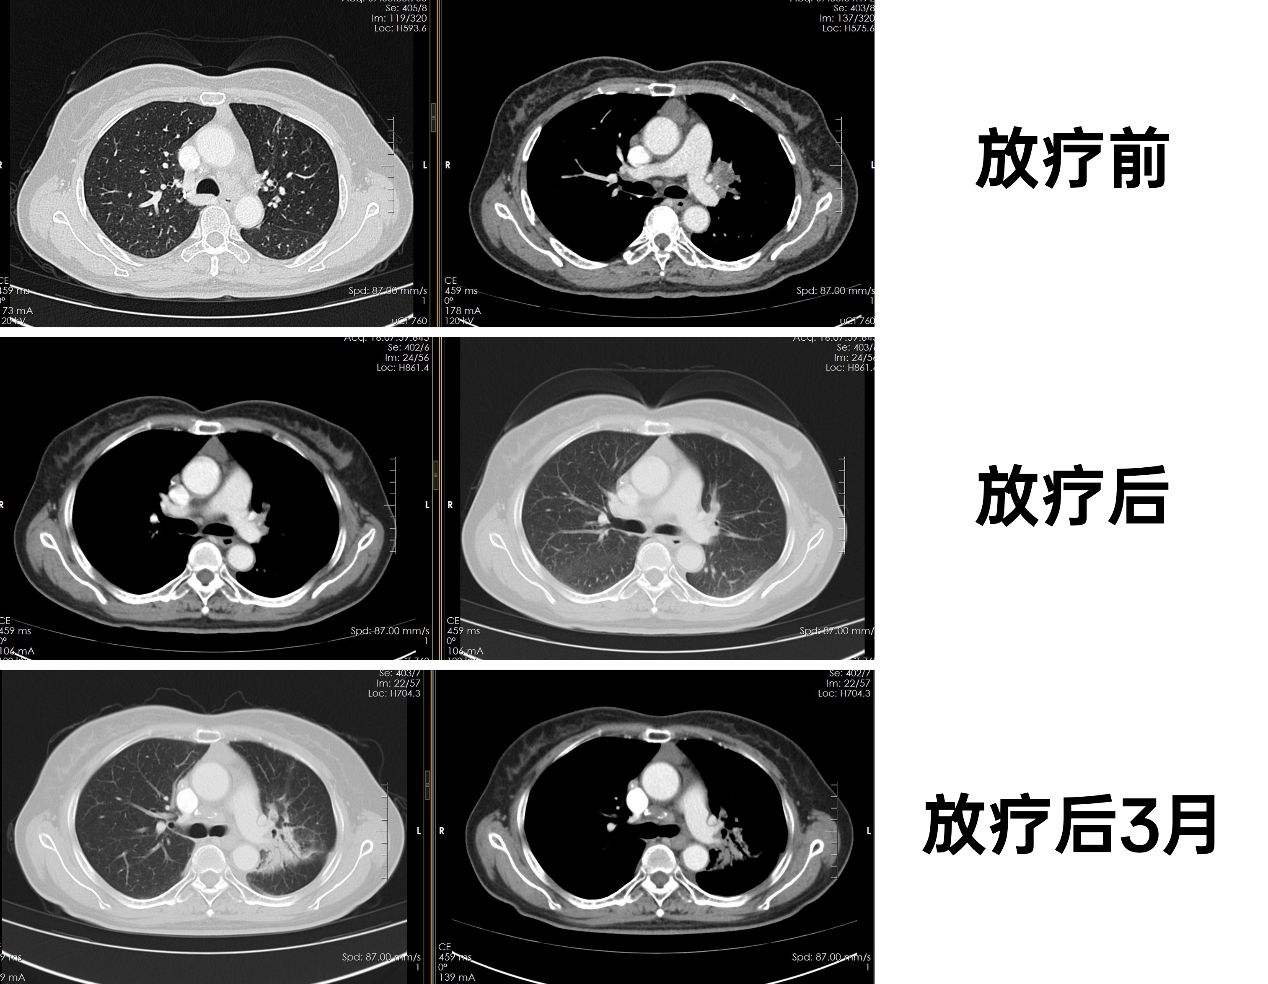

化疗前:2024-07-04,胸腹部CT:1. 左肺门占位,考虑中央型肺癌,并左上肺阻塞性肺炎,并肺门、纵隔淋巴结转移;右心隔角区小淋巴结,建议追观复查。2. 肝S4段稍低密度结节灶,转移瘤?肝S3段小片低密度灶,不典型血管?建议结合MRI检查。3. 双肾囊肿。4. 所示甲状腺右叶弱强化小结节,建议超声进一步检查。

放疗前:2024-10-16,胸腹部CT:1. 肺癌治疗后:左上肺门旁软组织密度影较前稍缩小,双肺门及纵隔淋巴结较前相仿。2. 右上肺小结节,炎性结节可能;右中肺钙化灶。3. 前纵隔软组织密度影同前,胸腺瘤或胸腺增生可能,建议复查。4. 肝左外叶部分肝内胆管扩张同前。5. 双肾囊肿同前。

放疗后1月:2025-02-12,胸腹部CT:1. 肺癌治疗后,现左肺炎性病变(考虑放射性肺炎)掩盖左上肺门旁软组织灶;双肺门及纵隔淋巴结较前相仿。2. 右上肺小结节同前,慢性炎性结节可能性大;右中肺钙化灶同前。3. 前纵隔软组织密度灶同前,胸腺瘤或胸腺增生可能,建议复查。4. 甲状腺右侧叶结节大致同前。5. 肝左外叶部分肝内胆管扩张同前。6. 左肾囊肿同前。

放疗后3月:2025-05-16,胸腹部CT:1. 肺癌治疗后,左肺炎性病变(考虑放射性肺炎)较前稍好转,掩盖左上肺门旁软组织灶;双肺门及纵隔淋巴结较前相仿。2. 右上肺小结节同前,慢性炎性结节可能性大;右中肺钙化灶同前,右中肺少许纤维灶。3.前纵隔软组织密度灶同前,胸腺瘤或胸腺增生可能,建议复查。4. 甲状腺右侧叶结节大致同前。5. 肝左外叶部分肝内胆管扩张同前。6. 双肾囊肿同前。